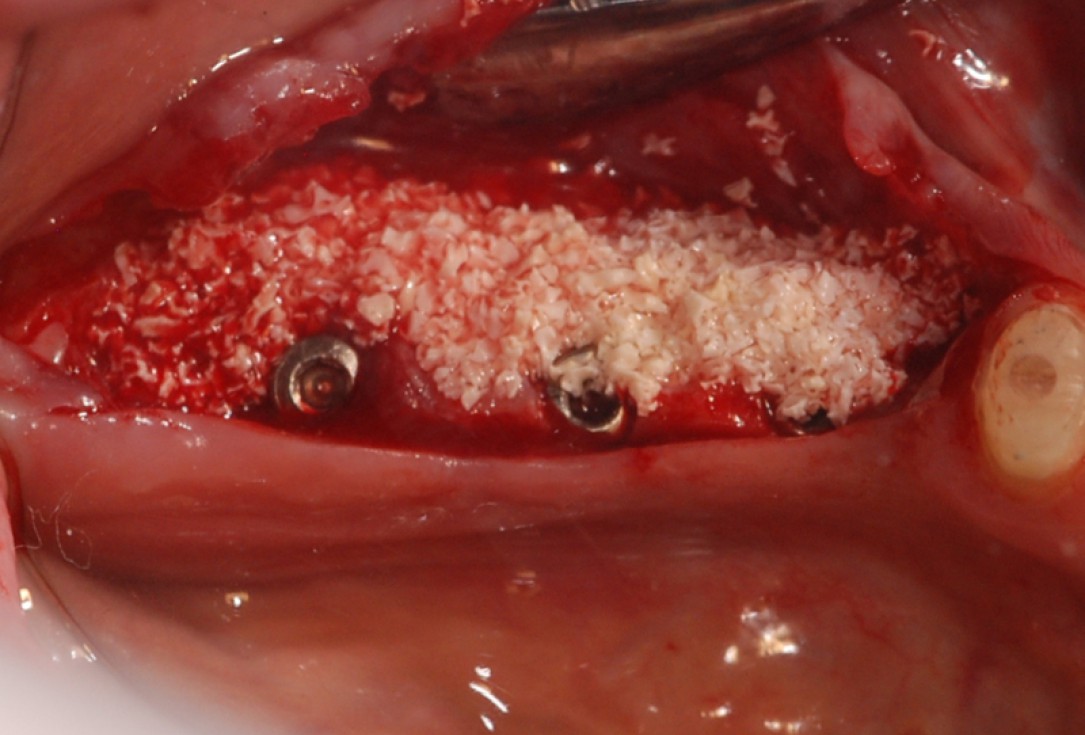

Three implants placed in a narrow posterior mandible